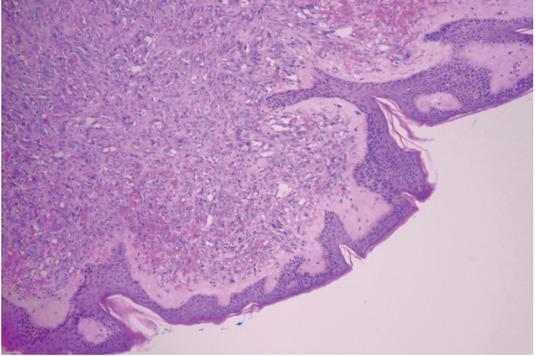

Figure 3